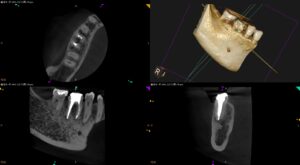

右下被せたばかりの歯が痛い…〜#30 Re-RCT 1回法

紹介患者さんの治療。 主訴は、 右下被せたばかりの歯が痛い… である。 患者さんの話によれば、 今までの根管治療は何度か通院したが痛みは取れなかった という。 が、痛みが軽度になったので最終的には被せたそうだ。 が、そこ … 続きを読む 右下被せたばかりの歯が痛い…〜#30 Re-RCT 1回法